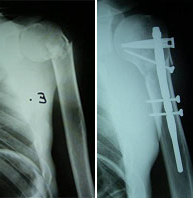

Aunque la región del hombro incluye la clavícula, el omoplato y el extremo proximal del húmero, son las fracturas de este último el grupo más importante por su frecuencia y relevancia. Las fracturas de la porción superior del húmero afectan con mayor frecuencia al paciente de edad avanzada por su menor densidad ósea y en mayor proporción al sexo femenino. En el paciente joven se asocia con traumatismos de alta energía como accidentes de tráfico y deportes de alto riesgo en los que se pueda producir un impacto directo de gran violencia como escalada, motociclismo, ciclismo, esquí, rugby, fútbol americano.El tratamiento dependerá del tipo de fractura y grado de desplazamiento. Las fracturas desplazadas suelen ser subsidiarias de tratamiento quirúrgico. En este caso una cirugía destinada a una movilización precoz con un riesgo mínimo de complicaciones exige un gran conocimiento de la biomecánica articular así como un meticuloso manejo de los tejidos adyacentes al hueso.